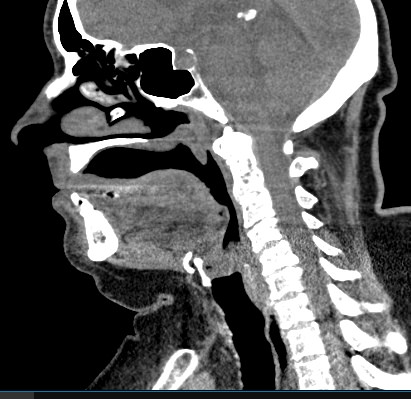

Мультиспиральная компьютерная томография – это высокоинформативный лучевой метод диагностики различной патологии мягких тканей шеи, включая воспалительные заболевания, травматические повреждения и опухолевые процессы. КТ позволяет оценить состояние щитовидной железы, паращитовидных желез, гортани, верхней части пищевода, шейных лимфоузлов и окружающих мягких тканей.

Метод КТ основан на применении рентгеновского излучения. Однако в отличие от обычного рентгена, при котором снимки производятся в одной плоскости, при КТ излучатель рентгеновских лучей постоянно двигается вокруг объекта исследования, проводя сканирование в различных плоскостях, а затем трансформируя полученные данные в цифровые трехмерные изображения. Это дает возможность визуализировать органы и ткани в мельчайших подробностях, а с помощью объемных 3D-реконструкций наглядно оценить пространственное расположение органов и патологических образований.

Рентгеновские лучи лучше всего поглощаются плотными структурами, такими как костная ткань. Поэтому кости хорошо видны на снимках КТ. Это делает компьютерную томографию незаменимой при необходимости обследования, в частности, костного скелета гортани. Однако для улучшения визуализации мягких тканей требуется введение специального контрастного препарата, поэтому КТ мягких тканей шеи в подавляющем большинстве случаев проводится с контрастным усилением.

Для контрастирования используется йодсодержащее контрастное вещество, которое в составе рентгеноконтрастного препарата вводится в вену пациенту непосредственно во время исследования. Благодаря способности контраста поглощать рентгеновские лучи на снимках КТ хорошо контрастируются кровеносные сосуды и опухолевые образования, имеющие, как правило, развитую сосудистую сеть. Методика внутривенного болюсного контрастирования помогает обнаружить воспалительные изменения, отличить доброкачественные опухоли от злокачественных, выявить поражение лимфатических узлов и степень прорастания опухоли в магистральные сосуды и окружающие ткани.